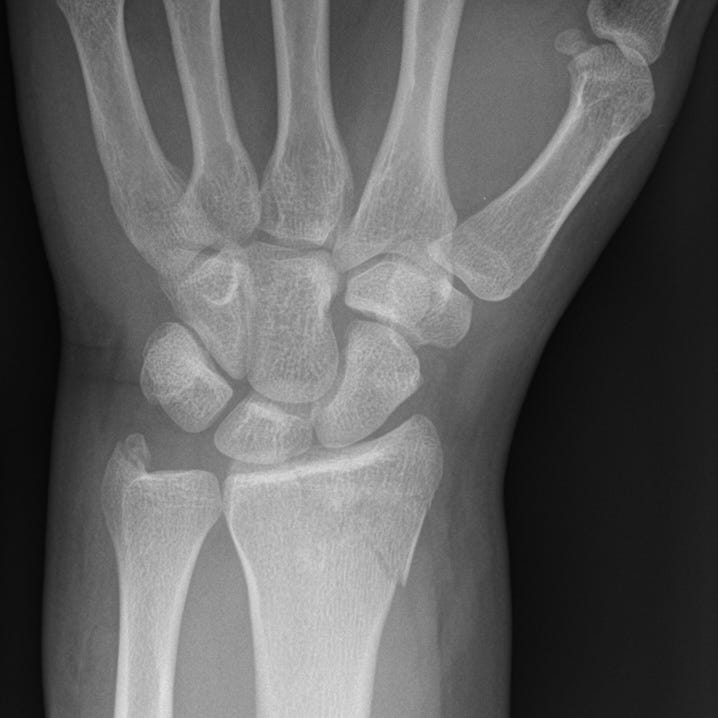

Distal Radial Fractures Pdf Skeletal System Musculoskeletal Distal radius fractures are classified according to (1) extension into the radiocarpal joint, (2) extension to the distal radioulnar articulation, and (3) the presence of an associated ulnar styloid fracture. Distal radius fractures are the most common orthopaedic injury and generally result from fall on an outstretched hand.

Distal Radial Fractures By Alexander Baxter Radnotes Acute distal radius fracture results in pain, tenderness, swelling and potential deformity. patients may be faced with substantial morbidity if fracture healing is delayed or results in clinically significant deformity. Distal radius fractures, commonly known as a wrist fracture, are defined by the involvement of the metaphysis of the distal radius. in younger patients, they are commonly associated with high energy mechanisms, and in older patients, they more frequently occur with lower energy mechanisms or falls. Common distal radial fractures home uw emergency radiology trauma radiology reference resource 09. upper extremity common distal radial fractures page views: 15,253. In this report, we have summarized the evidence on treatment and rehabilitation of distal radial fractures from the most recent available systematic reviews of high quality.

Distal Radial Fractures By Alexander Baxter Radnotes Common distal radial fractures home uw emergency radiology trauma radiology reference resource 09. upper extremity common distal radial fractures page views: 15,253. In this report, we have summarized the evidence on treatment and rehabilitation of distal radial fractures from the most recent available systematic reviews of high quality. Distal radial fractures are a heterogeneous group of fractures that occur at the distal radius and are the dominant fracture type at the wrist. these common fractures usually occur when significant force is applied to the distal radial metaphysis. A randomized, controlled trial of distal radius fractures with metaphyseal displacement but without joint incongruity: closed reduction and casting versus closed reduction, spanning external fixation, and optional percutaneous k wires. We review the evidence behind each guideline and highlight the practical implications of each guideline on care. This guideline is based upon 6 high quality studies, with 3 comparing different fixation techniques for complete intra articular distal radius fractures (jakubietz, yazdanshenas, hammer) and 3 comparing different fixation techniques for unstable distal radius fractures (marcheix, rozental, goehre).